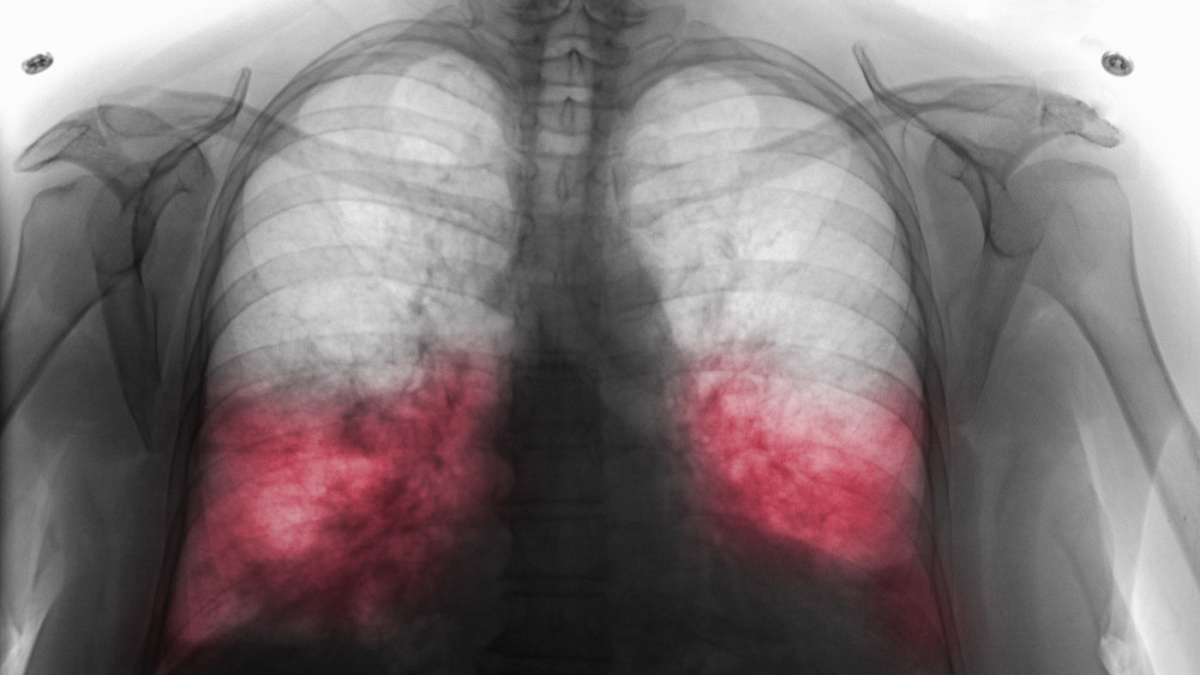

Zápalem plic onemocní v Česku každý rok až 120.000 lidí, ohrožuje hlavně seniory.

Mezi typické projevy patří horečka, kašel, bolest na hrudi, dušnost a celková schvácenost. "Abychom mohli říct, že pacient má zápal plic, musí být přítomny klinické příznaky a na rentgenovém snímku hrudníku také jasné změny. Pokud má pacient jen horečku a kašel, ale rentgen je čistý, jde o zánět průdušek, nikoliv plic," vysvětlil.